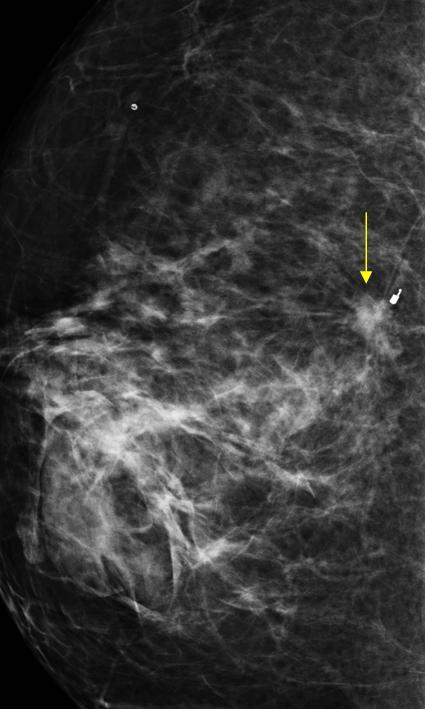

Ung thư vú

Ung thư vú - Ảnh 4

» Thông tin: Nữ giới – 62 tuổi.

» Lâm sàng: Kiểm tra sức khỏe.